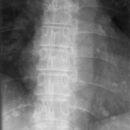

LWS a.p.

Es wurden keine Bilder gefunden.

Kassette/Abstand

Format 20/40 hoch / FFA 1,15m

Lagerung

Patient in Rückenlage, Arme längs des Körpers, durch Unterpolsterung oder Anziehen der Knie, Ausgleich der Lendenlordose. Zur Darstellung der ISF darf das Format nicht eingeblendet werden! Keine Bleischürze - falls möglich Hodenkapsel/Schmetterling

Zentralstrahl

Senkrecht auf WS und oberen hinteren Beckenkamm.

Indikation

Zwischenwirbelraum frei projiziert.

Qualitätskriterien

Scharfe und orthograde Abbildung aller Lendenwirbel mit ihren Querfortsätzen, der Kreuzdarmbeingelenke und des thorakolumbalen Überganges. Die Dornfortsätze sind mittelständig. Zwischenwirbelraum frei projiziert.